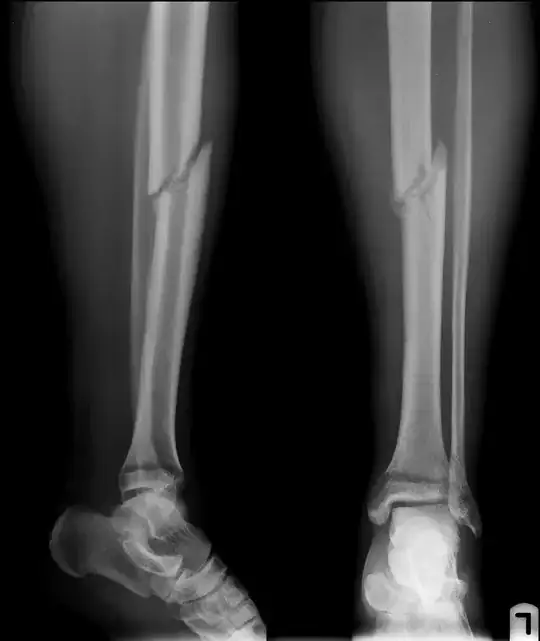

"Breaking" the fibula (or fibular ostotomy) in cases of tibial non-union is not unheard of, but I have absolutely no idea of how often it's done, or if the additional weight-bearing associated with it speeds tibial healing. But please note that you already have an angulated distal fibular fracture (look at the bone - the fibula - behind the tibia just above its concave surface in the leg on the left.) It looks to be at about 20°.

Also note that the tibial stress fractures - the fracture lines perpendicular to the plane of the tibial fracture itself - are more prominent in the second set of x-rays (this may just be picture quality), as well as more prominent displacement of your fracture, which is easier to see if you follow the medullary lines - the "hollow" inner part of the bone where the bone marrow is - you'll see they line up nicely in the first set of x-rays, less so in the second.